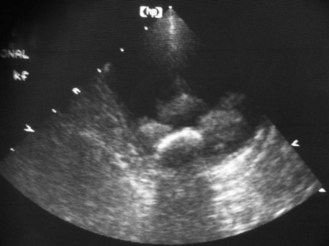

Procedure: Basic examination technique: Use of diagnostic ultrasound is a non-invasive painless procedure that is well tolerated by most animals. It can usually be administered to fully conscious patients, although its use for guiding fine or biopsy needles may require sedation or general anaesthesia. There have been no reports of adverse clinical effects in the patient or in the personnel involved in its use.

1. Action: Place the patient on an examination table in a position that provides sufficient access to the area under examination.

Rationale: This may mean that the patient may remain standing or lying in lateral or dorsal recumbency. If the patient feels secure and comfortable it will be less likely to struggle.

2. Action: Select an appropriate part of the body for examination.

Rationale: Choose an area of skin over the point of interest and where the depth of tissue that has to be crossed is minimal.

3. Action: Avoid choosing a site where bone or gas-filled structures lie between the skin and the point of interest.

Rationale: Both bone and gas will block the ultrasound beam and may affect image quality or impair visualization of deeper tissues.

4. Action: Clip the skin and clean with surgical spirit.

Rationale: Fur must be removed to ensure good contact between the transducer and the skin. Surgical spirit is used to remove grease and dirt.

5. Action: Apply liberal quantities of acoustic or coupling gel to the transducer and the skin.

Rationale: This ensures that there is good contact between the transducer and the skin; it is more important to apply gel to the skin than it is to apply it to the transducer. Any other material (e.g. air or dirt) will create another acoustic interface, which may affect the image. Concentric white lines on the resulting image indicate poor contact and the site should be prepared again.

6. Action: Apply the transducer to the skin in the prepared area moving it around as necessary.

Rationale: The strength of the returning echo depends on the nature of the tissues and the angle of the interface relative to the sound beam.